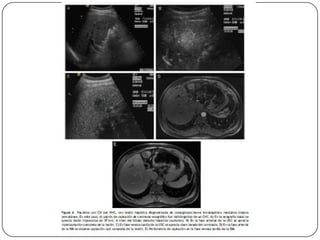

Auxiliares de diagnóstico

 USG

 Imágenes hipoecoicas, encapsuladas y con sombra

acústica, aunque en ocasiones aparecen como

alteraciones inespecíficas de la ecogenicidad, por

lo que resulta difícil diferenciarlas del daño

hepatocelular crónico.

 Sensibilidad (60-80%), Especificidad (45-96%)

 La sensibilidad en el CH alcanza 86%, pero en

lesiones menores de 2 cm es baja.

 Cada 6 meses en pacientes hepatópatas

 TAC

 Sensibilidad del 68% con especificidad de 93%, se

utiliza para precisar las alteraciones vistas en el

usg.